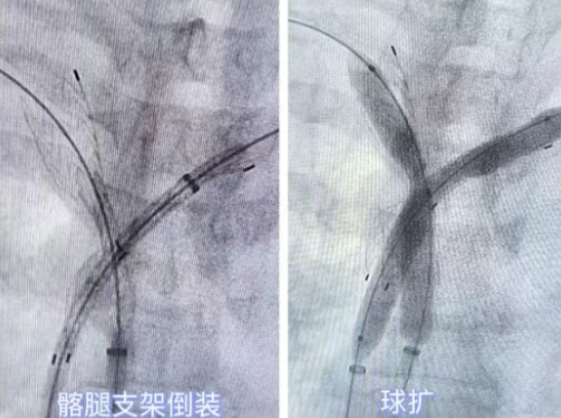

球囊扩张,初步疏通管腔。使用球囊导管对狭窄/闭塞部位进行了充分、渐进的扩张,初步恢复了部分血流通道,为支架置入创造了条件。

创新支架应用 - 覆膜支架倒装精准植入。这是本次手术的关键创新点,团队特别选用了覆膜支架,其优势在于能有效维持血管通畅性,减少内膜增生导致的再狭窄风险。更关键的是,考虑到姚女士个体化的血管解剖结构和病变特点,团队对支架进行了个性化处理,将支架拆下并进行了“倒装”(调整了支架的释放方向)。随后,经右侧股静脉送入一枚16*14.5*70mm**的覆膜支架,在狭窄/闭塞处精准定位并成功释放。这次“倒装”植入确保了支架的最佳贴壁性和对病变的最优化覆盖,最大程度地撑开了阻塞的血管腔,恢复了生理血流。

即时确认,效果完美。再次造影确认,支架位置理想,膨胀充分,覆膜完整覆盖病变区域,上腔静脉血流恢复通畅,手术取得圆满成功。